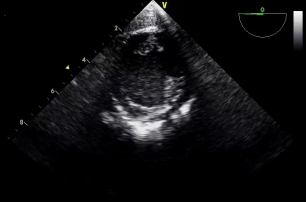

经食道超声心动图(TEE)是将超声探头置于食管内,经食道从心脏后方探查其结构,可避免胸壁、肺气等因素的干扰,可获得高质量的图像(图1),提高对心血管疾病诊断的敏感性和可靠性。